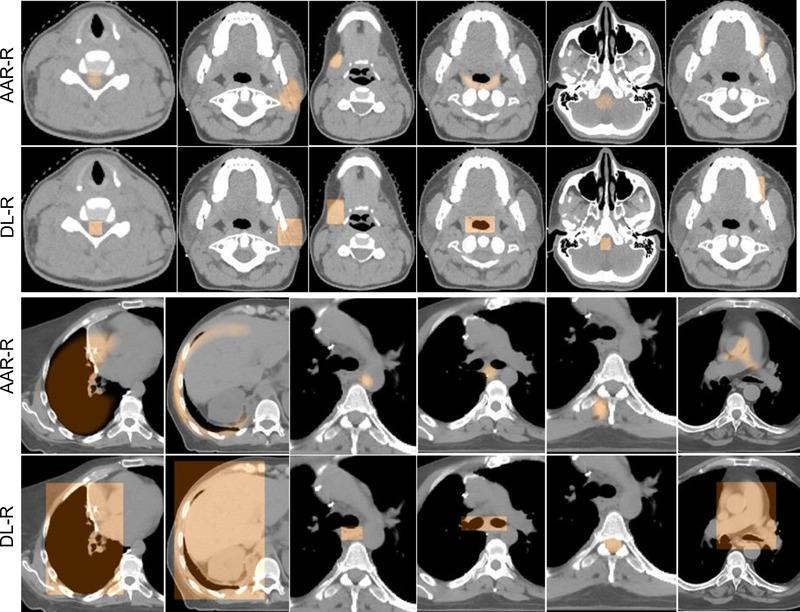

The system employs five modules: (i) body region recognition, which automatically trims a given image to a precisely defined target body region; (ii) NI-based automatic anatomy recognition object recognition (AAR-R), which performs object recognition in the trimmed image without DL and outputs a localized fuzzy model for each object; (iii) DL-based recognition (DL-R), which refines the coarse recognition results of AAR-R and outputs a stack of 2D bounding boxes (BBs) for each object; (iv) model morphing (MM), which deforms the AAR-R fuzzy model of each object guided by the BBs output by DL-R; and (v) DL-based delineation (DL-D), which employs the object containment information provided by MM to delineate each object. NI from (ii), AI from (i), (iii), and (v), and their combination from (iv) facilitate the HI system.

该系统采用五个模块:(i)身体区域识别,自动将给定的图像修剪到精确定义的目标身体区域;(ii)基于 NI 的自动解剖识别对象识别(AAR-R),在未使用 DL 的情况下对修剪后的图像执行对象识别,并为每个对象输出一个局部模糊模型;(iii)基于 DL 的识别(DL-R),细化 AAR-R 的粗识别结果,并为每个对象输出堆叠的 2D 边界框(BB);(iv)模型变形(MM),根据 DL-R 输出的 BB 引导每个对象的 AAR-R 模糊模型变形;以及(v)基于 DL 的描绘(DL-D),利用 MM 提供的对象包含信息描绘每个对象。(ii)中的 NI、(i)、(iii)和(v)中的 AI 及其(iv)中的组合有助于 HI 系统。